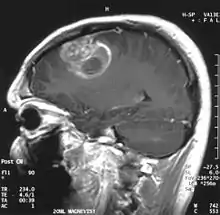

Glioblastome multiforme

Le glioblastome est la tumeur primitive du cerveau la plus fréquente et la plus agressive.

La tumeur peut prendre des apparences variées, en fonction de l'étendue de l'hémorragie ou de la nécrose, ou de son âge. Une scanographie (CT scan) montre généralement une masse non homogène avec un centre hypodense étendu en un anneau de taille variable entouré d'œdème. Il existe un effet de masse avec un déplacement possible du ventricule latéral et du troisième ventricule.